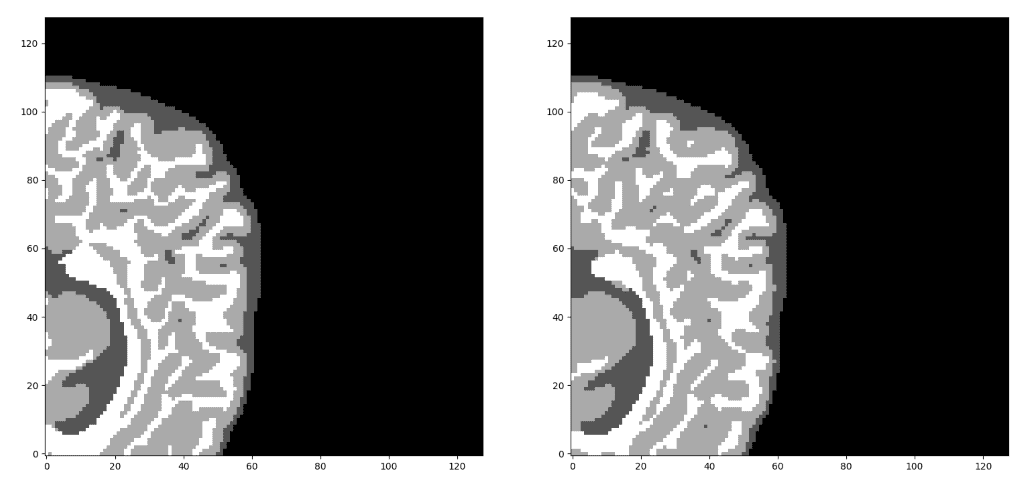

该模型在子卷的验证集中达到了大约 93% 的骰子系数分数。最后但同样重要的是,让我们看看验证集中 3D-Unet 的一些可视化预测。尽管预测是 3D 体积,但我们在这里只展示一个代表性切片。通过获取 MRI 的多个子体积,可以将它们组合起来形成完整的 3D MRI 分割。请注意,我们使用子卷采样的事实是数据增强。

我们的预测 VS 基本事实。您认为哪个预测是基本事实?仔细看看再做决定!需要注意的是,我们在这里只展示了中轴切片,但预测是一个 3D 体积。可以观察到,该网络完美地预测了空气体素,但难以区分组织边界。但是,让我们再次检查以找出真正的那个!

现在,我相信您可以区分基本事实。如果不确定,请查看文章末尾:)